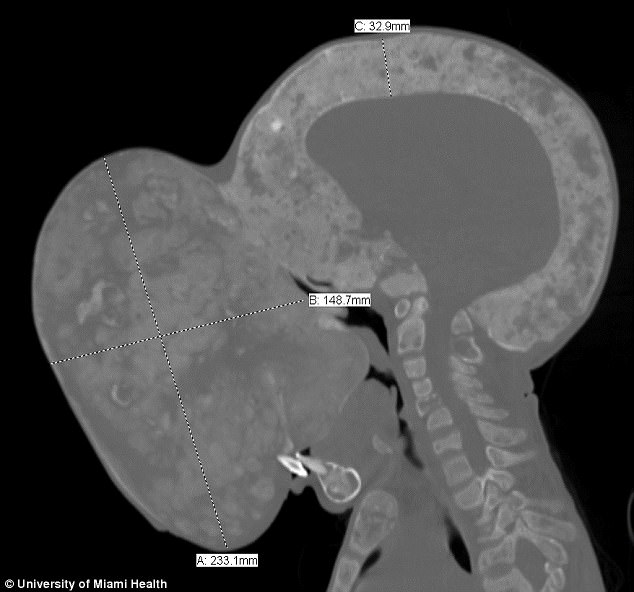

Se continuar a crescer, o tumor, que já está com pouco mais de quatro quilos, poderá sufocar o garoto e fraturar seu pescoço. O menino foi enviado à Miami com um visto médico para que possa passar por uma cirurgia em janeiro, segundo informações do Daily Mail.

Quando tinha 11 anos, o tumor de Zayas começou a ganhar tamanho a partir do nariz. Hoje, com 14, o tumor já está do tamanho de uma bola e gradualmente afetando a maneira como come, vê e fala, além de tê-lo deixado irreconhecível.

Embora se trate de um tumor benigno, ou seja, não cancerígeno, ele de fato ameaça à vida do garoto, uma vez que o crescimento gradual poderá sufocá-lo e fraturar seu pescoço.

No momento, Emanuel só pode respirar pela boca e, porque o processo de mastigação é muito complicado, está extremamente desnutrido. Ainda, o tumor é tão grande que bloqueia sua visão, permitindo-lhe olhar apenas para cima e lados.